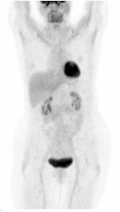

PET — Anterior Pancoast Tumor

FDG-PET showing intense uptake in an anterior Pancoast tumor (superior sulcus) of the lung

PET Downloaded 2026-03-15

Pet

Fdg

Wikimedia Commons: Anterior Pancoast tumor PET.jpg